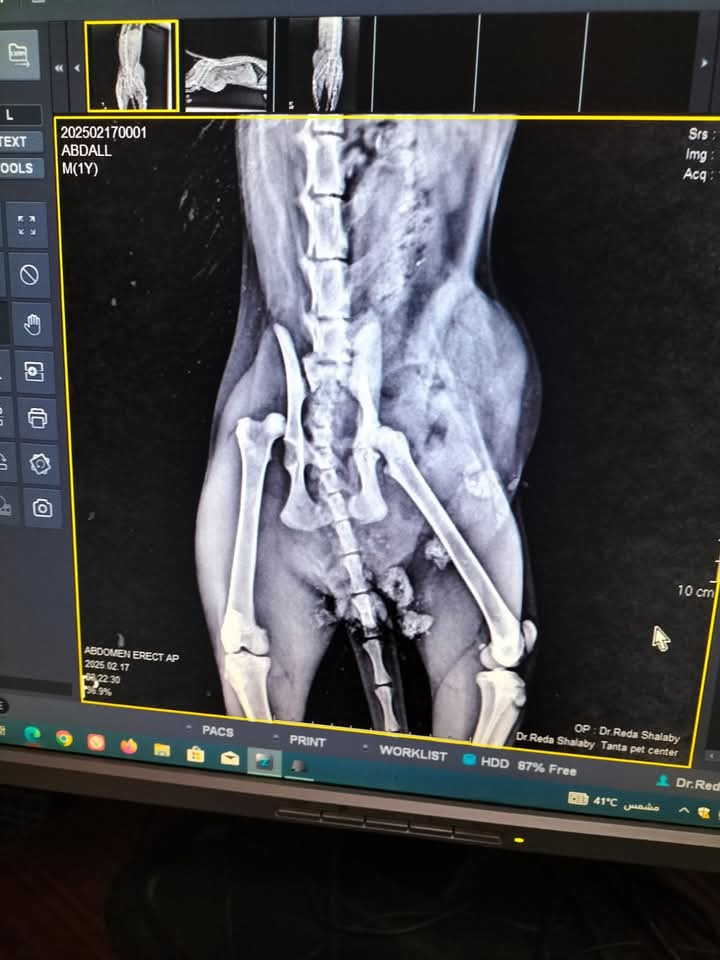

أجرى فريق أطباء عيادة طب وجراحة الحيوانات الأليفة، بديوان عام مديرية الطب البيطرى بالغربية، جراحة لإصلاح فتق اربى بجدار البطن باستخدام شبكة جراحية، لقط نتيجة لحادث سيارة أدى إلى احتجاز والتصاق الأمعاء الدقيقة والمثانة داخل غلاف الفتاق، والذى أدى ايضا لحدوث كسر بعظام الحوض، وخلع فى مفصل الحوض للرجل اليمنى على أن يتم التعامل الجراحى لكسر الحوض وخلع المفصل فى مرحلة لاحقه عقب استقرار الوضع الصحى للحالة واكتمال تعافيها من الجراحة الأولى Right Inguinal Hernia repair with polypropylene surgical mesh

الاشعة للقط

الاشعة